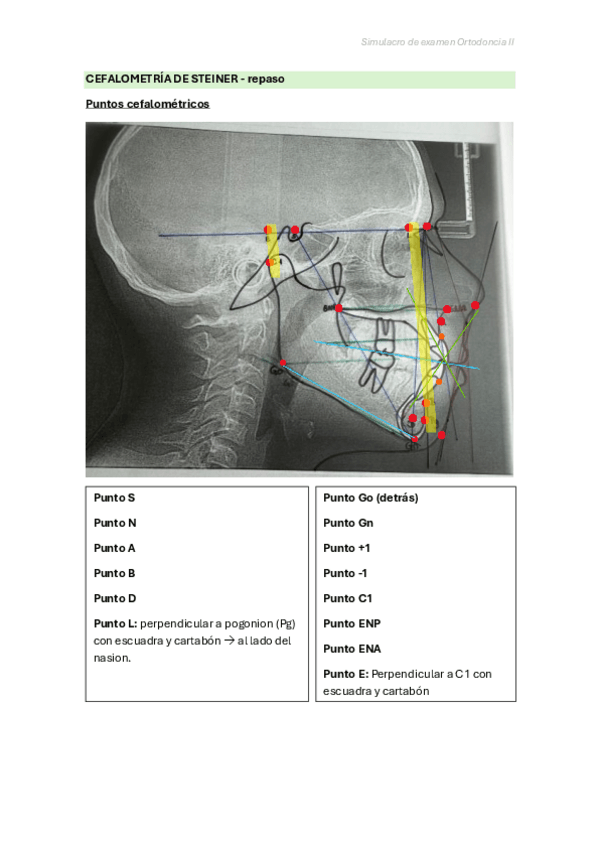

Repaso rápido para cefalometría de steiner

4 páginas